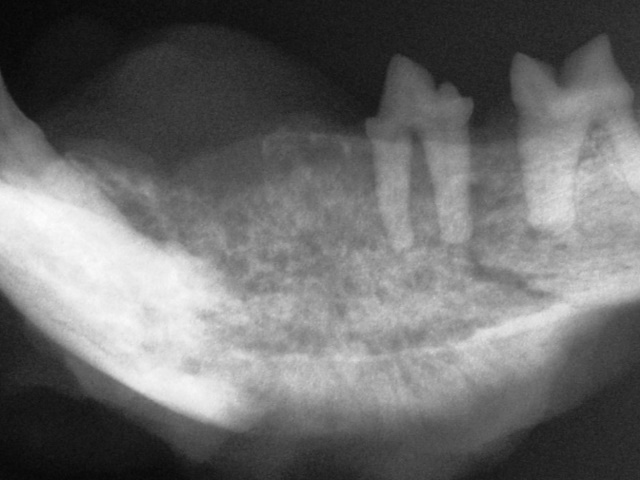

The mandible of a cat shows severe, diffuse, poorly marginated bone destruction with loss of normal bone architecture consistent with an aggressive process. Biopsy showed squamous cell carcinoma.